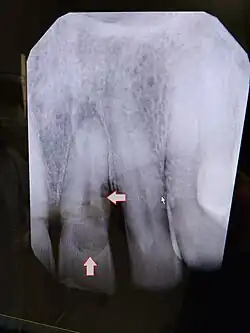

![]() Resorción externa incisivo central 21 | ||

Reabsorción externa

La reabsorción externa es la pérdida de la estructura dental de la superficie externa del diente. Se puede dividir en las siguientes clasificaciones:[4]